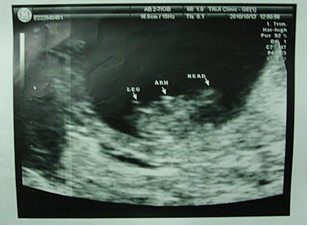

卵巣機能が良くない私は、気楽にできる自然周期体外受精を行い、受精に成功したのは5つの胚でした。移植当日には、張先生は私達を連れて、胚が受精している状況を見せくれて、移植に適した4つを選びました。